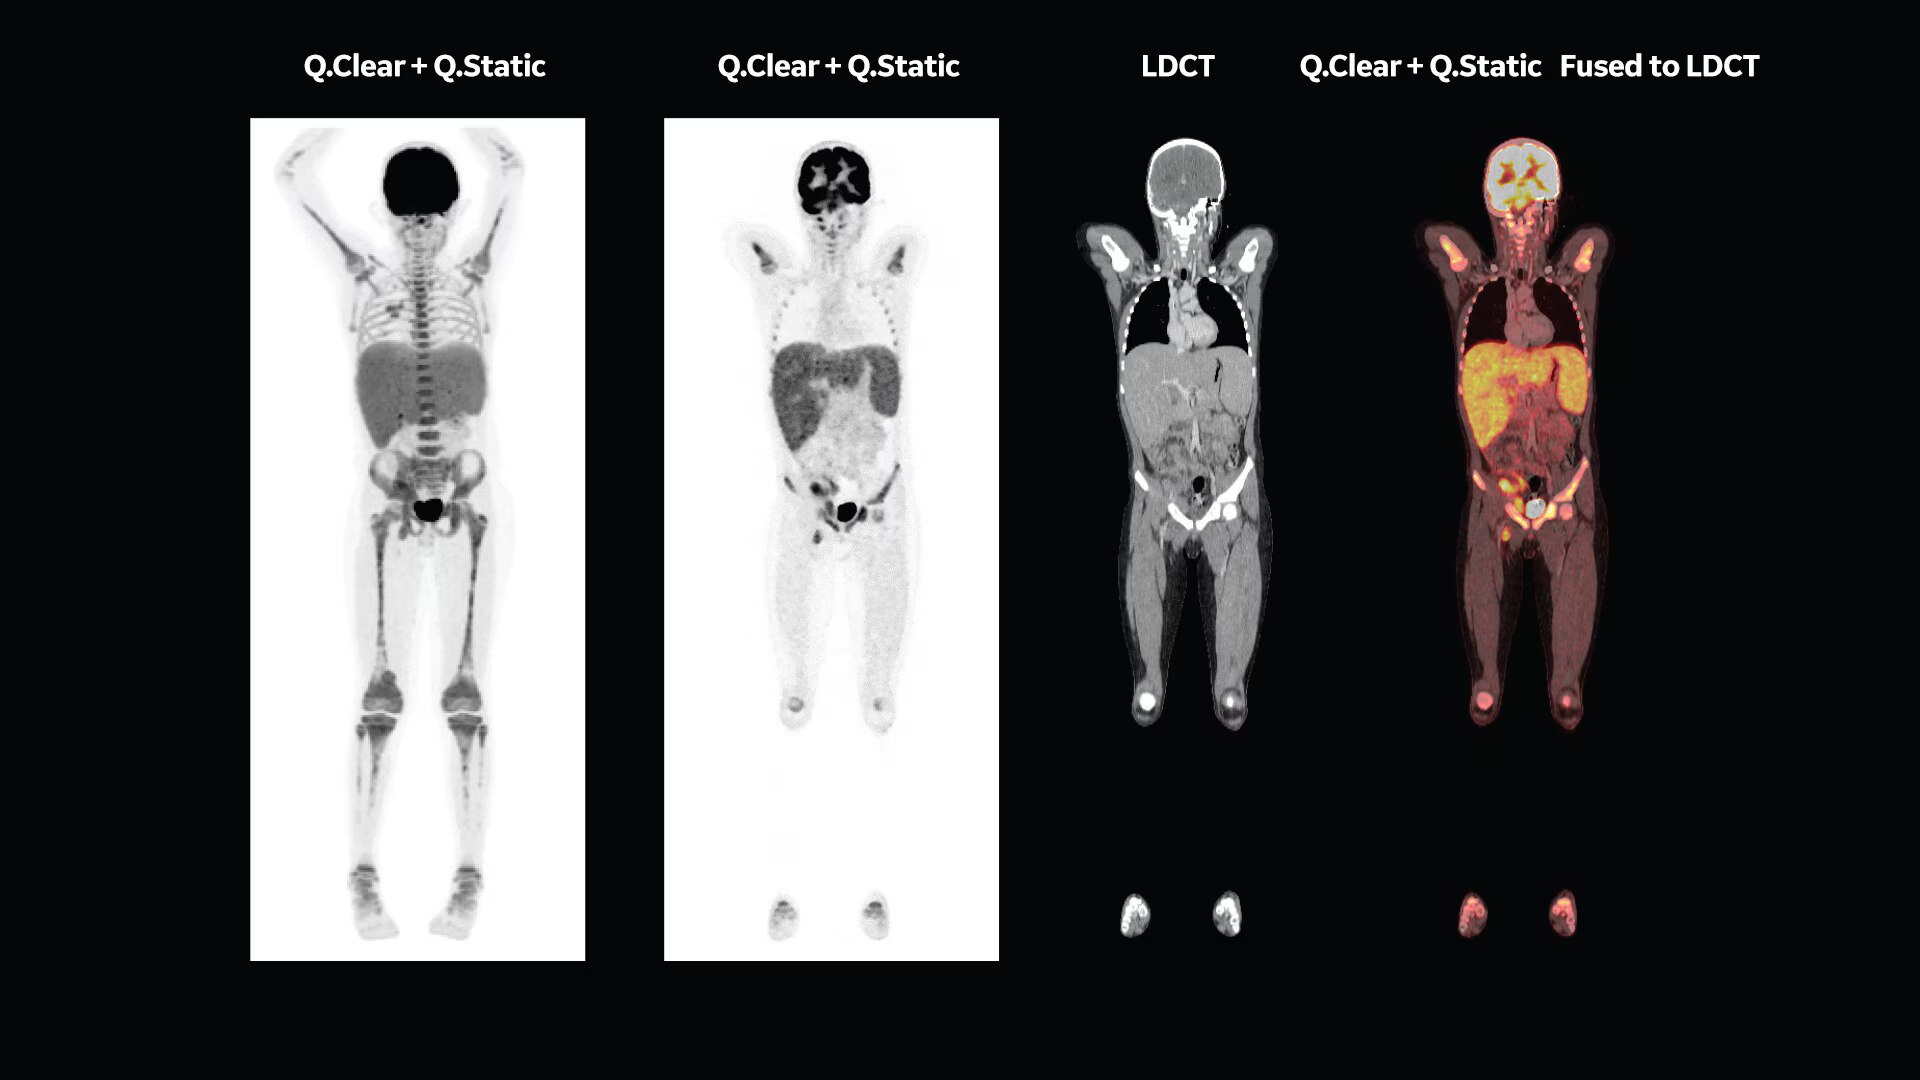

Whole-body Dynamic IQ Protocol

A whole new way to scan

Static whole-body PET/CT imaging provides a simple snapshot of radiopharmaceutical concentration, but it takes time to truly understand how tissue is behaving. With whole-body dynamic imaging, you can see the difference between tracer activity that’s simply trapped in tissue versus highlighting actual malignancies. Capturing this level of information takes time. Discovery MI Gen 2 delivers the FOV and the sensitivity necessary to enhance whole-body dynamic acquisition. It allows you to capture as much detail as possible in fewer bed positions. With Discovery MI Gen 2 and WB Dynamic IQ Protocol4, you have a powerful new tool that provides you with the ability to better identify regions of metabolic activity and increased tracer uptake rate5.